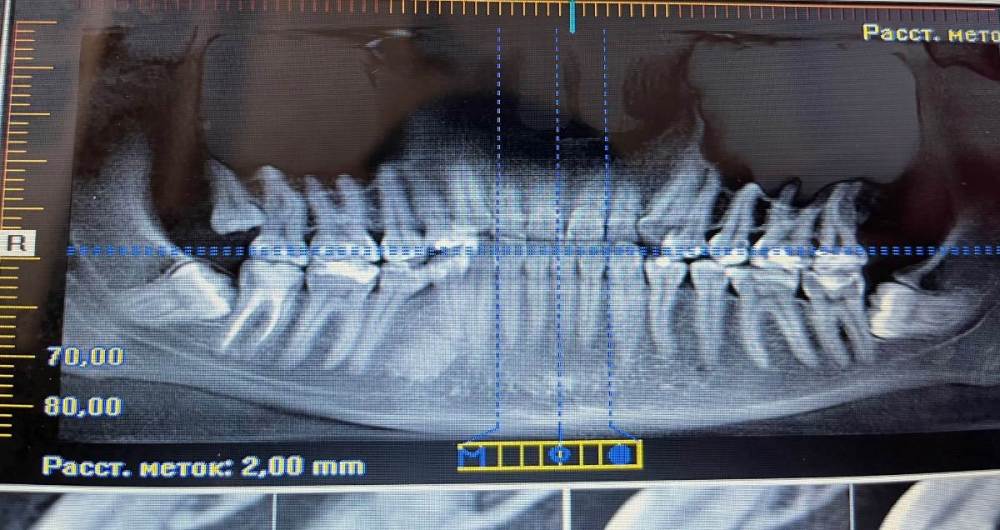

Александра30 Опубликовано 8 ноября, 2023 Поделиться Опубликовано 8 ноября, 2023 Здравствуйте, несколько месяцев назад обратилась к ортодонту с целью выравнивания зубного ряда и прикуса. При выполнении КТ обнаружено образование в нижней челюсти в районе 28 и 29 зубов, все склоняются к варианту остеомы ( которое ортодонт настоятельно рекомендует удалять ввиду возможной спаянности с корнем 4ки) и три ретенированных 8ки. Консультировалась с ЧЛХ( один из самых авторитетных хирургов в области): рекомендует удалять 8ки, а остеому наблюдать, т.к сложная операция, рядом подбородочный нерв и будет необходимо замещение костной ткани. Ну а продвижению 4ки это образование никак не помешает. Ну и собственно вопрос: возможно ли ортодонтическое лечение без удаления образования или обратиться за вторым мнением ЧЛХ? Ссылка на комментарий

Александра30 Опубликовано 8 ноября, 2023 Автор Поделиться Опубликовано 8 ноября, 2023 Со слов ортодонта, по срезам образование очень близко с корнем 4ки, хирург в этом проблемы не видит, а самой в срезах достаточно сложно сориентироваться Ссылка на комментарий